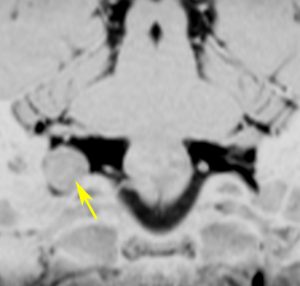

症例:小脳延髄角槽のもの,頸静脈孔へ少し入るもの

30歳くらいの女性に発生した無症状のものです。矢印のように拡大した頸静脈孔へ少し入っています。定位照射でもよかったかもしれませんが,若い女性なので手術しました。

脳槽部迷走神経根から発生したと考えて,外側後頭下開頭で摘出しましたが,予想外に延髄に近い部分の迷走神経から剥がせず,ほんの少し神経根の上に残しました。術後10年経ちますが腫瘍再燃はありません。聴神経腫瘍で顔面神経の上に薄く腫瘍を残すのと同じ考え方です。